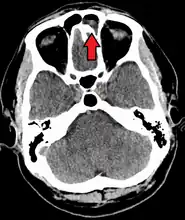

Frontal sinusitis -